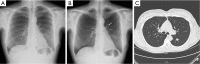

Figure 2

Digital chest tomosynthesis image showing a solid pulmonary nodule in a 63-year-old man. (A) The pulmonary nodule is not visible on the postero-anterior chest radiograph; (B) digital chest tomosynthesis showing a right basal nodule (white arrow), confirmed by CT scan (C) and PET (D). After the VATS lobectomy, the pathological examination showed the presence of a squamous cell carcinoma.